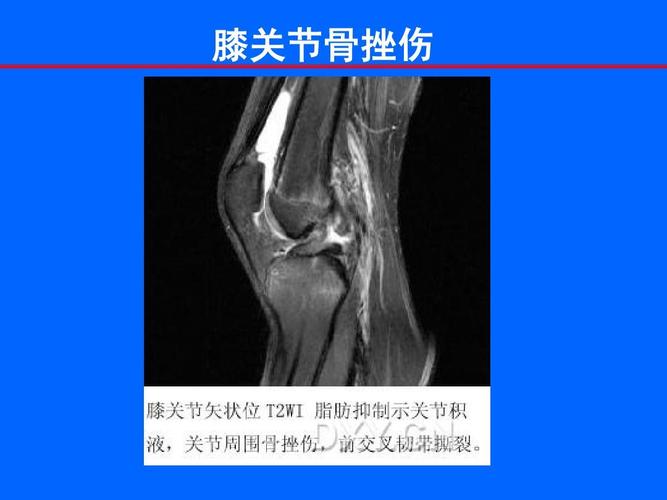

膝关节骨挫伤

患者膝关节磁共振影像,大片白色亮斑即为骨挫伤.

胫骨骨挫伤